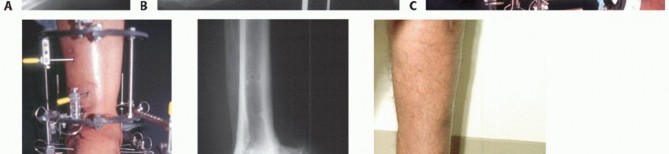

- The arthrodesis must be in a plantar neutral position. A fusion with the foot in equinus will severely compromise the functional outcome (FIG 4).

- FIG 4 • A. Tibiocalcaneal arthrodesis with loss of talar head and navicular in crush injury of foot. B. Full lateral x-ray of tibia and foot is accurate method to evaluate foot position. With no ankle motion and compromised forefoot motion, aligning the foot in plantar neutral position and correct forefoot rotation is

essential for a functional result. Observe mature proximal bone transport to equalize leg length.

A delayed shortening is then carried out until the arthrodesis is compressed (FIG 5). The patient is encouraged to mobilize the forefoot and toes and knee.

FIG 5 • A. Lateral x-ray of bifocal external fixator. The proximal tibia has been lengthened between the ⅝-full ring block and the double-ring block on the midtibia. B. Lateral x-ray of the tibiocalcaneal arthrodesis with compression between the midtibia and the footplate. The foot is in plantar neutral alignment. C. Mature tibiocalcaneal arthrodesis with the plafond fused to the calcaneus and navicular. D. AP x-ray with axial alignment of arthrodesis. The patient had a valgus deformity after frame removal of the transport. The tibia was realigned with a lateral locked plate.